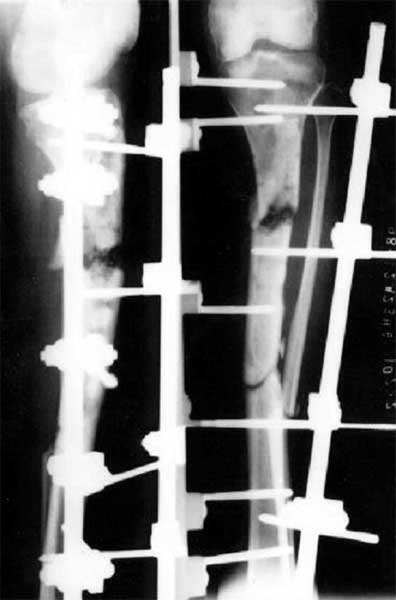

胫骨多段骨折外固定架术后1年,形成骨不连。取除外固定架,

改用髓内钉固定,6个月后骨折愈合。